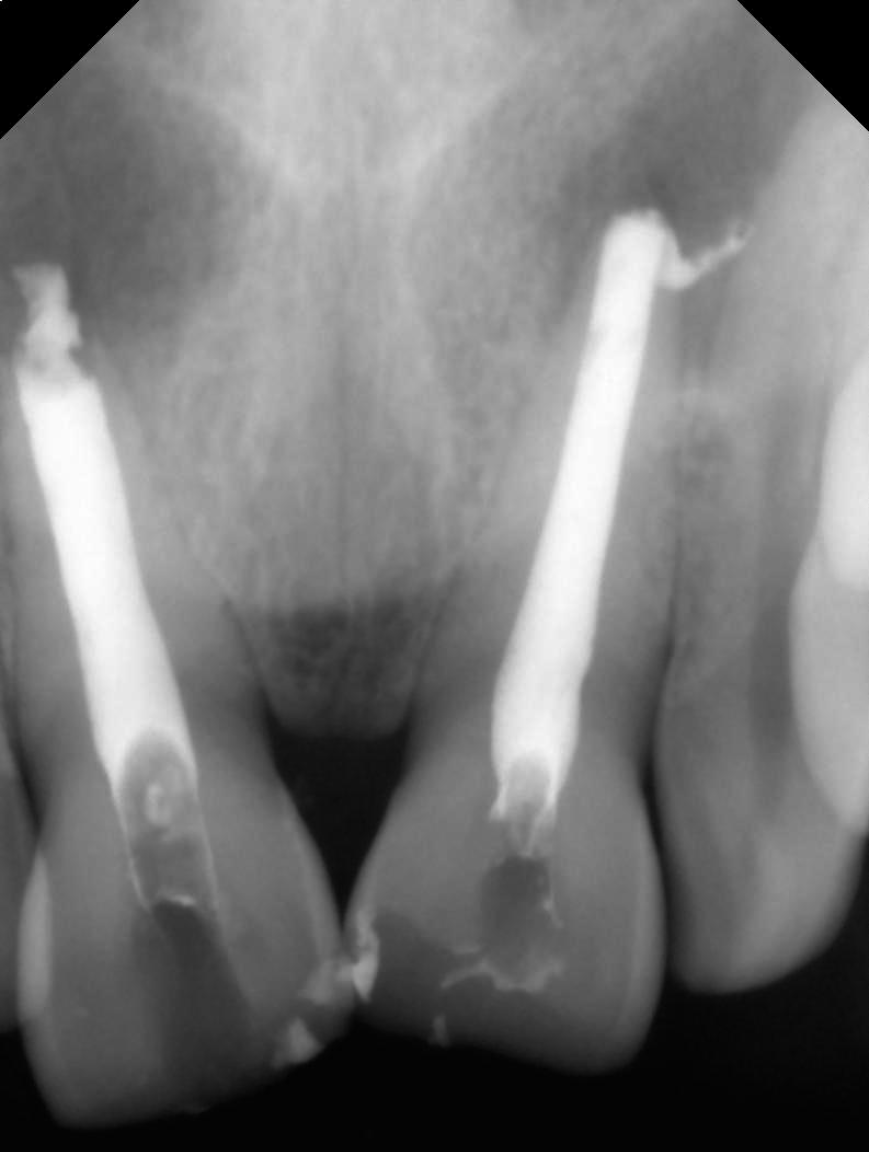

Figure 3 Shows the working length wrt 11 and 21.